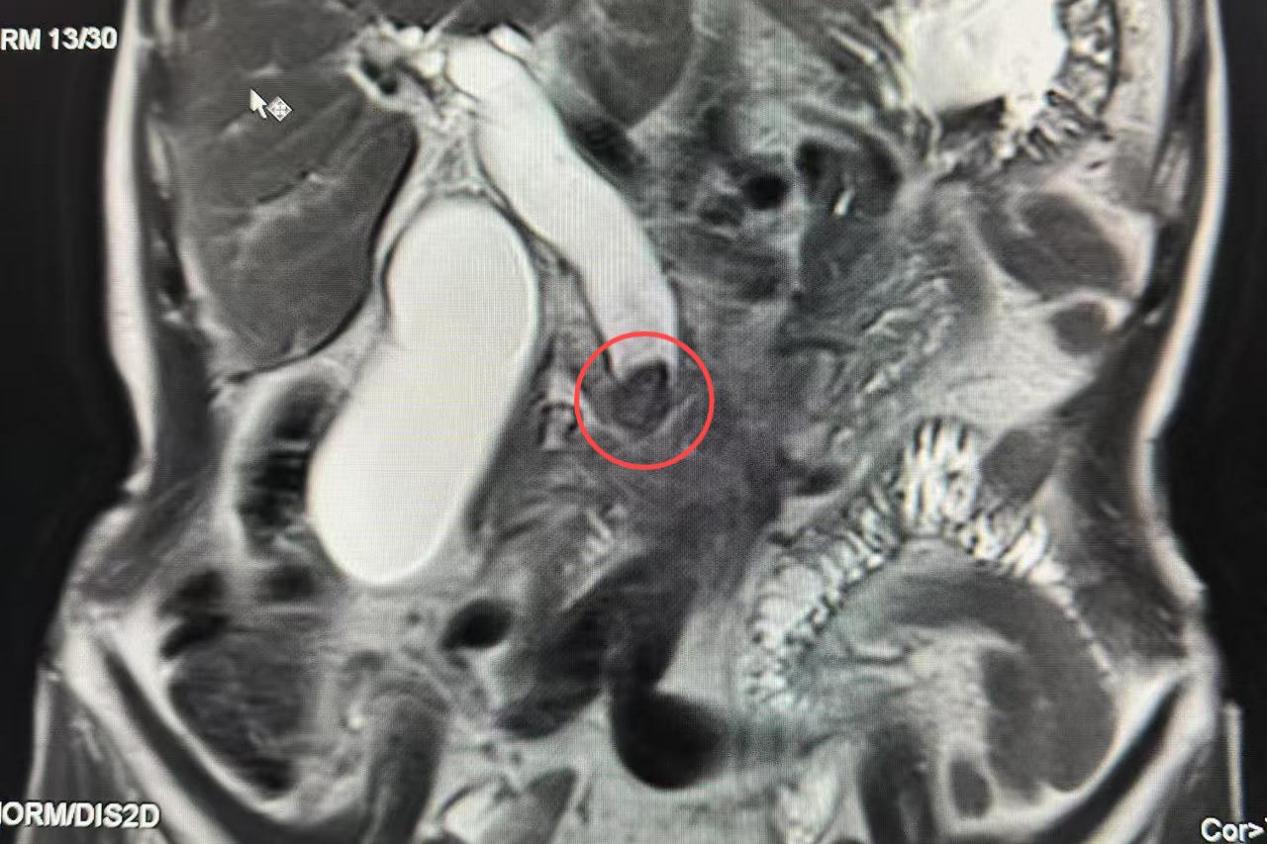

CT影像示肝外胆管扩张,胆总管下段结石嵌顿(红圈处)

3月2日,当腹痛如绞的症状首次发作时,这个操着浓重湘音的老人做了所有务工者都会做的选择:强忍——直到忍不住疼痛,吴伯才来到坪山区中心医院急诊科就诊。值班医生在CT影像上发现胆总管内嵌顿的结石,警报骤然拉响。“必须马上住院!”接诊医生的话让老人攥紧了衣角——他身上没有多余的钱,手术费用像块沉甸甸的石头,压在了他的心上。

放射科专家指着CT片上扩张的胆总管,麻醉科专家反复测算生理指标,普外科团队模拟着手术路径。多学科会诊室内,读片灯的冷光映照着一份份签满专家姓名的会诊记录,最终方案一锤定音:立即为吴伯实施开腹胆总管切开探查取石术+胆囊切除术。